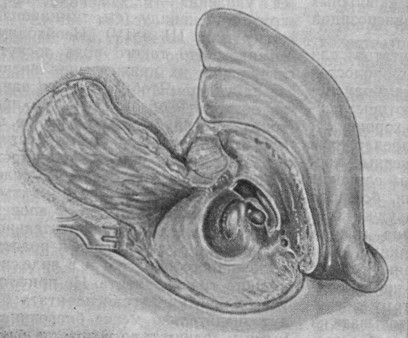

Анатомия сосцевидного отростка